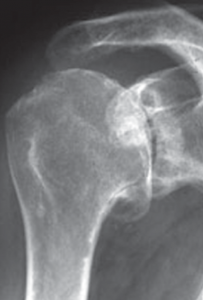

Der klassische Verschleiß des Schultergelenkes tritt im Vergleich zum Hüft- und Kniegelenk beim älteren Menschen seltener auf. Hierbei erfolgen eine Zerstörung des Gelenkknorpels und die Deformierung der Gelenkflächen, die zu einer schmerzhaften Bewegungseinschränkung des Schultergelenkes führen (Abb. 34, 37).